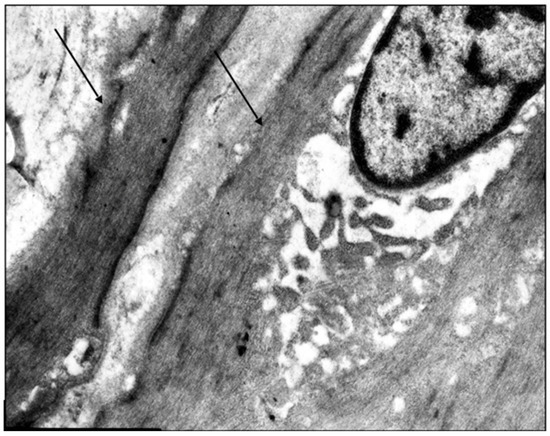

Age- and Varicose Disease-Associated Changes in the Muscular Components of the Great Saphenous Vein

by Khurshed A. Abduvosidov, Irina A. Chekmareva, Valeria G. Shestakova, Irina N. Shabanova, Alexander G. Alekseev, Edgar S. Kafarov, Alexander A. Palalov, Irina N. Yashina and Evgeny N. Galeysya

J. Clin. Med. 2025, 14(18), 6448; https://doi.org/10.3390/jcm14186448 - 12 Sep 2025

Varicose disease and other age-related vascular illnesses are extremely prevalent among the adult population. Despite this, research devoted to involutive changes in the veins of the lower extremities is rare and fragmented. Complex morphological evaluation of the wall of the vein related to [...] Read more.

Varicose disease and other age-related vascular illnesses are extremely prevalent among the adult population. Despite this, research devoted to involutive changes in the veins of the lower extremities is rare and fragmented. Complex morphological evaluation of the wall of the vein related to age and varicose disease can add valuable data to fundamental geriatric and vascular medicine. Objectives: The study was designed to determine the age-related changes in the muscular component of the great saphenous vein and changes associated with varicose disease. Materials and Methods: A morphological study of a specimen of the great saphenous vein was conducted on 55 deceased individuals and 80 patients with varicose disease. Four age subgroups were identified: young, middle-aged, elderly, and senile. A total of 135 fragments of the great saphenous vein were evaluated. Histological, morphometric, and electron microscopic studies were performed. A quantitative analysis of the volumetric fraction of muscular components was calculated using the Shapiro–Wilk test, Kruskal–Wallis (ANOVA) and Mann–Whitney methods with Bonferroni correction. Results: Our study showed that the amount of connective tissue elements between bundles of smooth muscle cells increased with age. In patients with varicose disease, we observed an appearance of connective tissue fibers among smooth muscle cells, more pronounced with the disease progression. The structure of smooth muscle cell changes. Thus, we observed hypertrophy and phenotypic heterogeneity of cells with subsequent destruction of communicative contacts. The values of subintimal longitudinally arranged smooth muscle cells reached their maximum in middle age in both normal and varicose veins, while significant decrease occurred in elderly and senile patients. Quantitative indicators of circularly arranged smooth muscle cells of the middle layer did not change with age but significantly decreased in varicose disease. Age-related changes are characterized by an increase in the proportion of smooth muscle cells in the outer layer. In varicose veins, in young and middle-aged patients, the content of bundles of longitudinally arranged smooth muscle cells in the outer layer was higher compared to the age norm, with a significant decrease in senile age. Conclusions: The age norm of the muscular component of the great saphenous vein wall is characterized by an increase in the volumetric fraction of subintimal longitudinally arranged smooth muscle cells in middle age, the volumetric fraction of circularly arranged smooth muscle cells of the middle layer remains unchanged, and the volumetric fraction of bundles of longitudinally arranged myocytes of the outer layer increases. With age in varicose disease, sclerotic changes progress in the structure of the great saphenous vein at the tissue, cellular, and intracellular levels, leading to a decrease in the volumetric fraction of all muscular components of the great saphenous vein structure. Full article